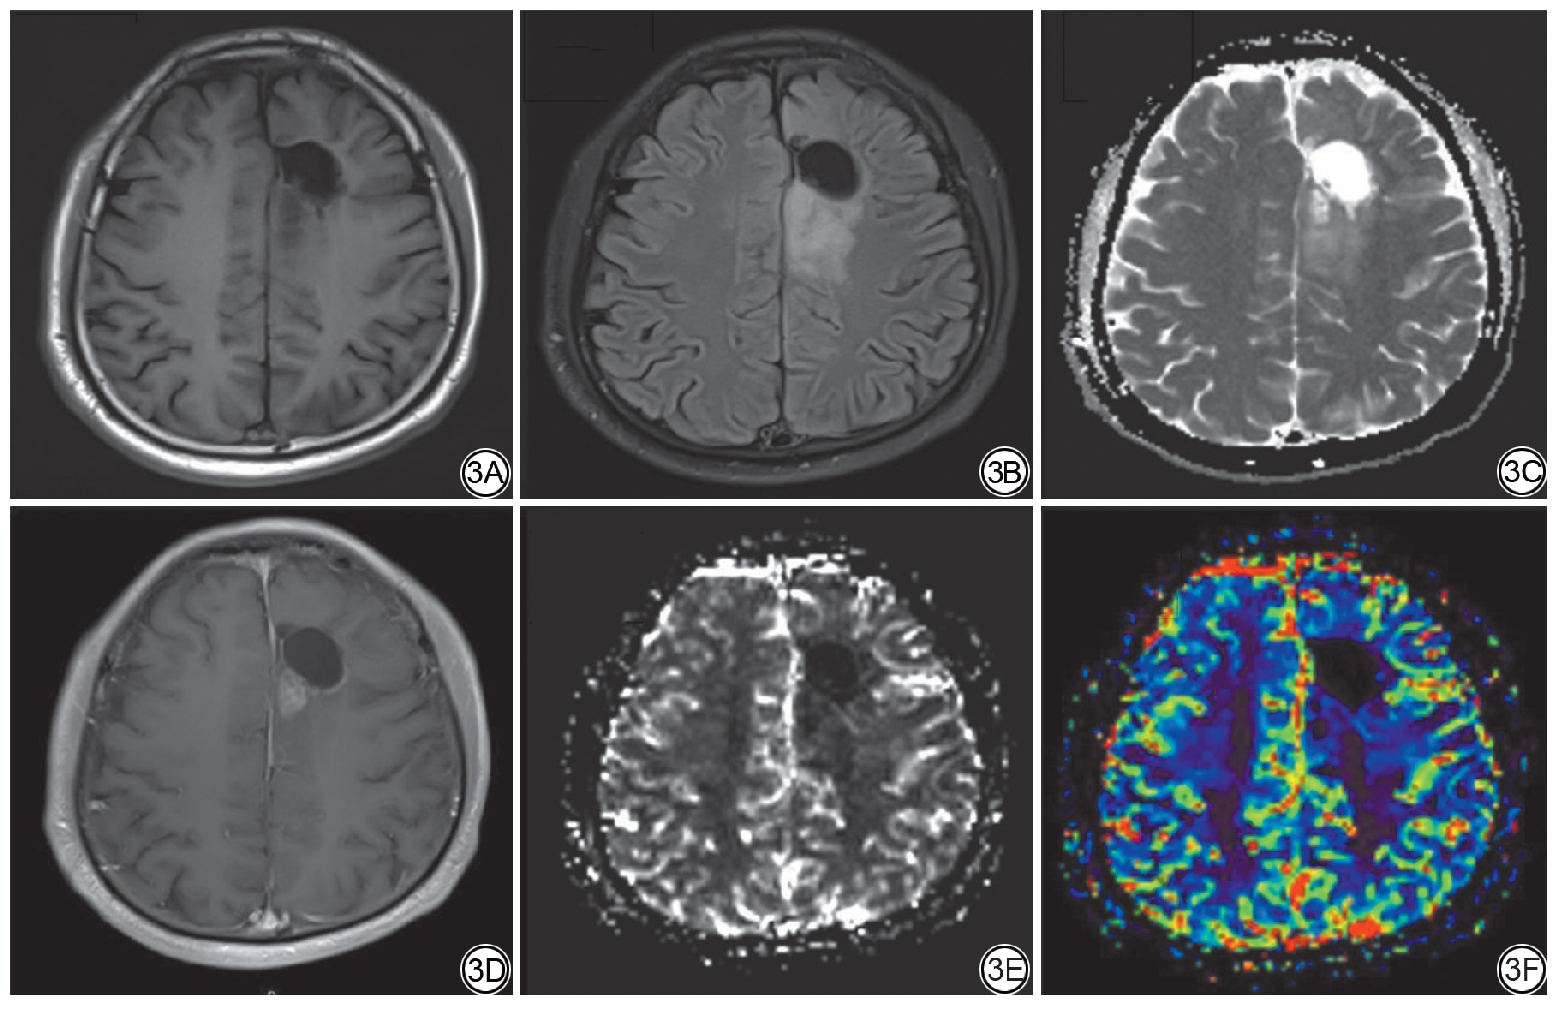

在本研究纳入的106例患者中,TP组65例,PsP组41例,其中二次手术病理证实为TP 9例,证实为PsP 8例,典型影像学表现见图2, 图3。脑胶质瘤术后TP及PsP均表现为术区或邻近脑组织内团块状、斑片状T1WI低信号、T2WI高信号,增强扫描呈明显不均匀强化,均可见占位效应,但肿瘤复发灶周围水肿范围较PsP明显,且病灶大多弥散受限,表现为不同程度的高灌注。患者临床影像资料见表1。2位医师对病灶定位、病灶中心部位的评估一致性良好(Kappa值分别为0.93、0.89,P<0.001),对病灶强化体积测量的一致性优秀(ICC=0.90,P<0.001),表明影像评估结果可靠。

图3  高级别胶质瘤术后假性进展典型MRI 表现。图3A~3F 分别为病变在轴位T1WI、FLAIR、ADC、CE-T1WI、CBV、CBV-RGB 序列上的显示。左侧额叶术区后缘见一强化灶灌注未见明显增高。FLAIR:液体衰减反转恢复;ADC:表观扩散系数;CE-T1WI:T1 加权对比增强成像;CBV:脑血容量。

Fig. 3  Typical MRI manifestations of postoperative recurrence in high-grade glioma. Figures 3A-3F demonstrate the lesion on T1WI, FLAIR, ADC, CE-T 1WI, CBV, and CBV-RGB sequences, respectively. A contrast-enhancing lesion without significant hyperperfusion is observed along the posterior margin of the surgical cavity in the left frontal lobe. FLAIR: fluid-attenuated inversion recovery; ADC: apparent diffusion coefficient; CE-T1WI: T1-weighted contrast-enhanced imaging; CBV: cerebral blood volume.